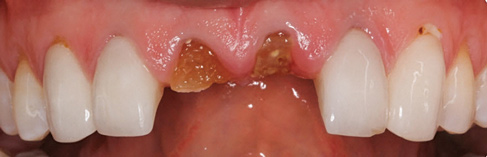

A 29-year-old Caucasian woman presented to the author's (GAM) practice for evaluation of teeth Nos. 8 and 9. The teeth were fractured at the free gingival margin and had sclerosed dental pulps (Figure 7 and Figure 8). The patient's medical history was significant for gastroesophageal reflux disorder (GERD), migraines, narcolepsy, attention deficit hyperactivity disorder (ADHD), and depression. She had no known drug allergies or drug idiosyncrasies and was determined to have an American Society of Anesthesiologists (ASA) II physical status.

Fig 7. Initial examination of nonrestorable maxillary central incisors, clinical presentation.

Figure 7